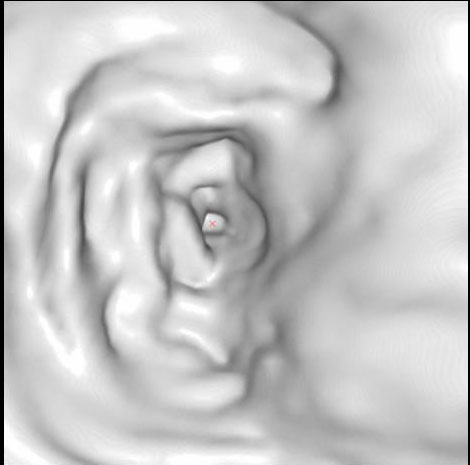

Циркулярный рак тонкой (подвздошной кишки)

Необходимо отметить, что данная патология довольно редко встречается, как правило выявляется на операционном столе у пациентов с тонкокишечной непроходимостью. На данном примере демонстрируем, что дефект кишки был диагностирован на основании 3D реконструкции, а затем уже целенаправленно подтвержден сканограммами с протяженностью процесса и степенью сужения кишечной трубки. Сыграла свою роль сопутствующая патология, которая имела место быть, а именно слабость Баугиниевой заслонки, за счёт чего тонкий кишечник полностью заполнился газом, хотя целью исследования было исключить патологию толстого кишечника.

Просвет тонкой кишки до и после дефекта в 3D-эндоскопе